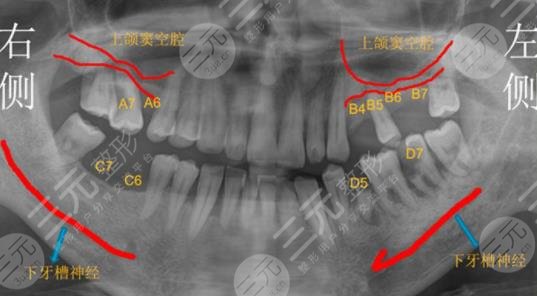

我的牙齿由于之前经常吃一些损伤牙齿的东西,后来也没有注意到保护牙齿的问题,所以导致吃饭的牙齿脱落情况较为严重。现在已经严重的影响到吃饭的问题,起先也打算做一些假牙和镶牙的项目,但是后来在网上查询发现这种项目做完之后持久度不长,较好还是做一些种植牙手术项目,所以我就在网上查询,发现我们这里的泰康拜博口腔医院在种植牙技术上已经很成熟了。

在种植牙的过程中,我较为害怕牙齿清洁不到位,会导致牙齿种植之后,各种发炎的情况,但是医生在为我做牙齿清洁的过程中耗费了大量的时间保障,没有细菌之后才为我做种植牙手术项目。

现在我已经种了三颗种植牙了,吃饭的时候感觉和其他的牙齿没有什么区别,颜色也和其他好的牙齿很搭配,在这里做种植牙手术项目的费用也是比较能接受的。